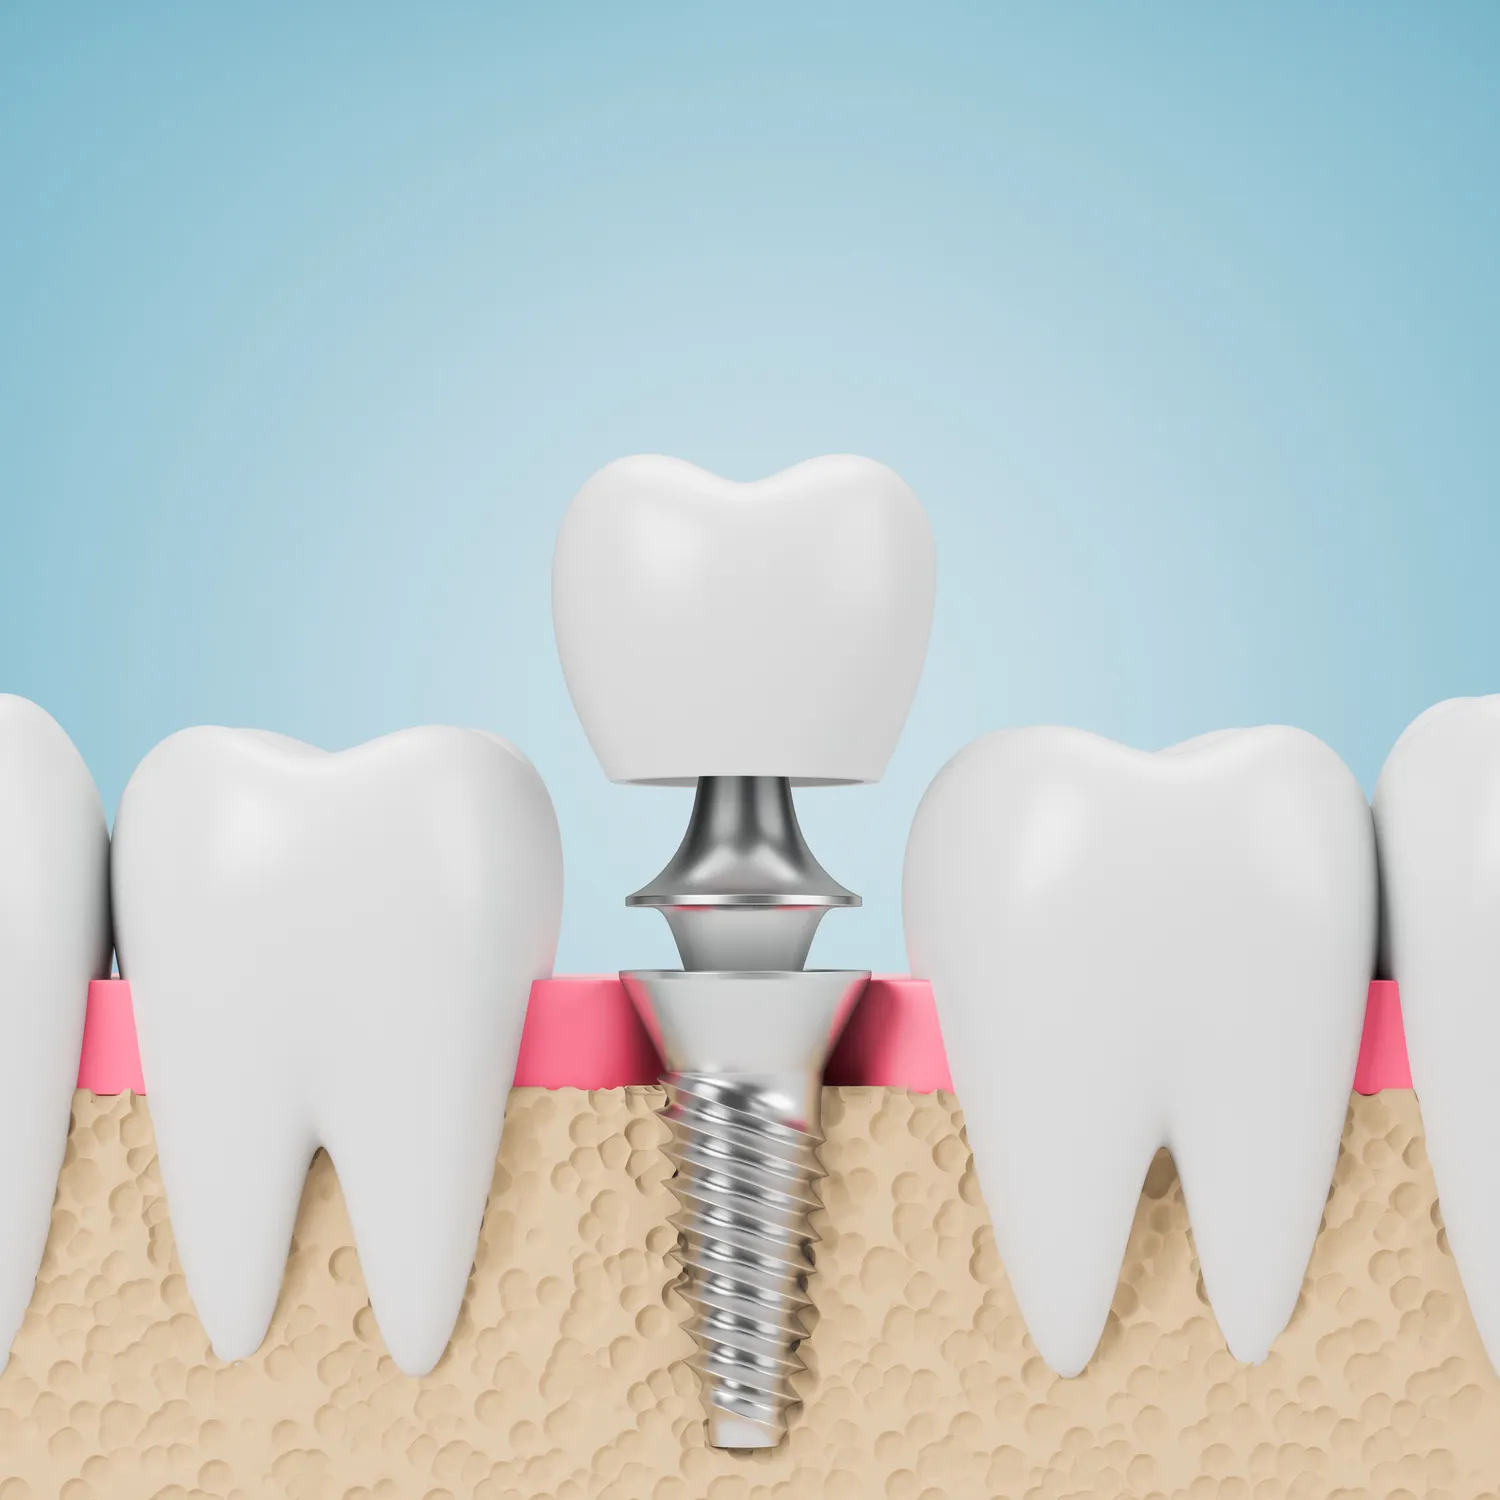

Leczenie kanałowe jest jedną z najskuteczniejszych metod ratowania zębów przed ekstrakcją, jednak istnieją także inne opcje terapeutyczne, które mogą być rozważane w zależności od stanu zęba oraz preferencji pacjenta. Jedną z alternatyw jest ekstrakcja zęba, która może być zalecana w przypadkach, gdy ząb jest mocno uszkodzony lub infekcja jest zbyt zaawansowana. Po usunięciu zęba można rozważyć zastosowanie implantów dentystycznych lub mostów protetycznych jako sposobu na przywrócenie funkcji żucia oraz estetyki uśmiechu. Inną opcją są zabiegi regeneracyjne, takie jak terapia komórkowa czy zastosowanie biomateriałów, które mają na celu odbudowę uszkodzonych tkanek. Warto również wspomnieć o metodach zachowawczych, takich jak stosowanie leków przeciwbólowych oraz antybiotyków w przypadku łagodnych infekcji.